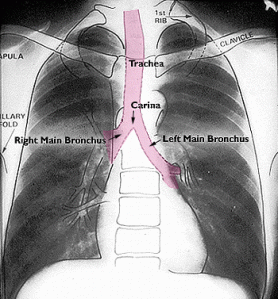

The other frustrating thing about dealing with chest x-rays is sometimes the radiologist tells you something is there that you can’t actually, you know, see. For instance, when you evaluate an X-ray, you have to identify the “carina” as an important point of reference. “Carina” is the fancy medical word for the point where your trachea branches off into the two bronchi, the main tubes supplying the lungs.

For orientation, here’s a cartoon of the carina:

The carina is where the pink tube splits in two, in case you’re like me and need everything explained like you’re five. It seems like you should be able to clearly pick this branch point out, right? Especially if you know roughly where it’s supposed to be. In lecture, Mr. Excited Radiologist demonstrated the branches with some helpful lines, which I have replicated here (same normal X-ray as before):